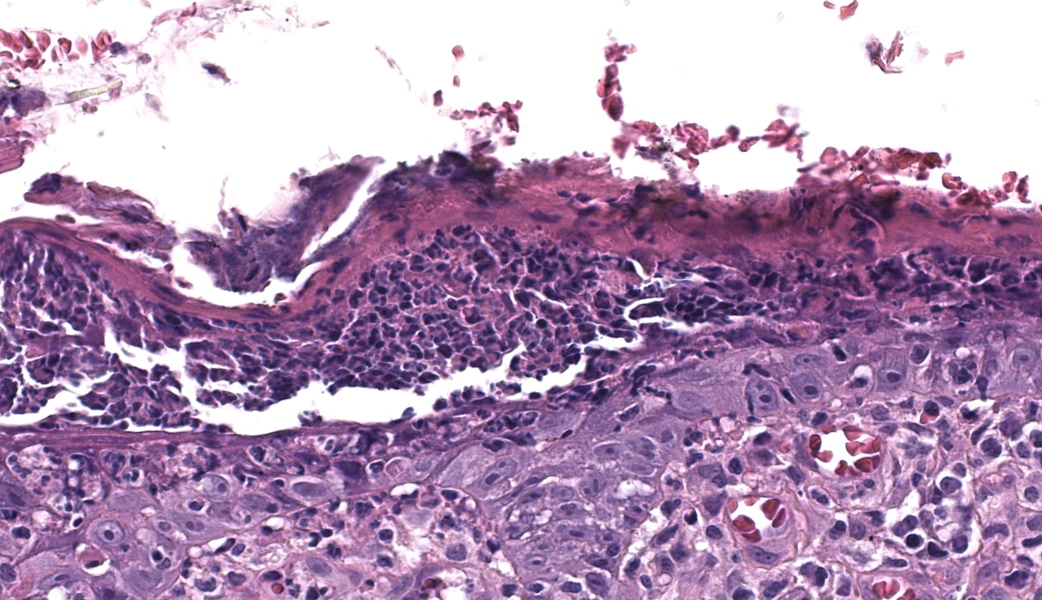

Haired skin. Alle the biopsies are histologically similar. The superficial and mid dermis is obscured by a moderate to severe inflammatory infiltrate, often obscuring the dermo-epidermal junction. The inflammatory infiltrate is represented by a prevalence of lymphocytes and plasma cells, macrophages occasionally engulfing melanin (melanophages), and rare neutrophils. The epidermis is moderately thickened (irregular hyperplasia), with mild intercellular edema (spongiosis) and severe thickening of the stratum corneum by predominantly nucleated (parakeratotic hyperkeratosis) or less frequently non-nucleated keratin (orthokeratotic hyperkeratosis). Numerous apoptotic figures are observed throughout the epidermis, occasionally surrounded by lymphocytic satellitosis. Similar lesions are observed in the hair follicles. There is multifocal erosion or ulceration of the epidermis; the ulcerated areas are obscured by serocellular crusts.Contributor's Morphologic Diagnoses:

Histologically, EM has the features of a cytotoxic (interface) dermatitis. Necrotic keratinocytes are present throughout the epidermis and the adnexal epithelia, often associated with lymphocytic satellitosis. The dermopidermal junction is obscured by lymphocytes and macrophages. Basal keratinocytes could be degenerated.3,5,6 Hyperkeratosis and parakeratosis are commonly seen in canine EM, as opposed to human EM, and may be severe in persistent forms of EM.6 This latter form is called “hyperkeratotic EM”.1

This classic case of erythema multiforme (EM) was much appreciated by participants as it stimulated great discussion on EM and other top differentials, cytotoxic dermatitis pathogenesis, and a handful of “boards-worthy” information. The contributor’s well-written and thorough comment covers much of what was discussed in conference related to the differences between the human and canine manifestations of EM, so focus will be placed on other major discussion points.The major histologic features to help differentiate EM from other conditions are the presence of suprabasilar and transepidermal apoptosis of keratinocytes and satellitosis of lymphocytes around affected keratinocytes.5 Note, however, that if lymphocytes are instead aggregating in and near the epidermis rather than just hovering around affected keratinocytes, epitheliotropic T-cell lymphoma should rise on the differential list. In EM, epithelial dysplasia may also be seen secondary to the concurrent inflammation and necrosis. The same features of transepidermal apoptosis and lymphocyte satellitosis can also be seen in the follicular epithelium, not just in the epidermis! Follicular epithelium may also exhibit hyperpigmentation and vacuolation secondary to inflammation. Parakeratotic hyperkeratosis is often seen in the hyperkeratotic form of EM but is not considered a key diagnostic feature of EM in general.1,5

Clinical photographs and a thorough history are crucial to dermatopathology cases as a whole and, when it comes to hyperkeratotic EM, can significantly help with diagnosis. Grossly, canine EM typically appears as red papules to plaques that are centrally cyanotic and present on the trunk, groin, and axilla. Hyperkeratotic canine EM, however, can look like raised, hyperpigmented, lichenified plaques in similar locations, but predominantly affects the face and ears. The current school of thought is that hyperkeratotic EM is idiopathic and may target suprabasilar keratinocytes with subsequent proliferation of basilar cells that results in the parakeratotic hyperkeratosis seen histologically.1,6